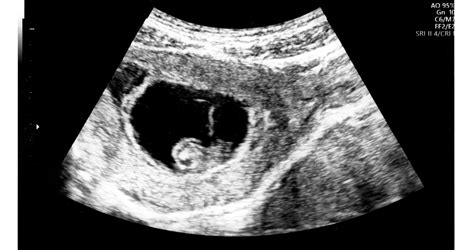

Vizsgálatok a 20. héten

A 20. hétre esik a sorrend szerinti negyedik terhességi vizsgálat időpontja, ahol a súly- és vérnyomásmérés mellett megmérik a méhcsúcs és a szeméremcsont távolságát is. Ez a mérőszám a baba növekedésének ellenőrzésére szolgál. Az ultrahangvizsgálat során az egészségesen fejlődő magzat látványa segíthet a szülők megnyugtatásában és motivációt adhat arra, hogy jobban figyeljenek egészségükre. A babamozi a várandósság minden szakaszában más-más élményt nyújt. Legideálisabb a 23-30. hét között beiktatni.

A magzat kb. 16-20 cm, amely egy padlizsán hosszának felel meg. Súlya 250-290 g, amely egy kocka vaj súlyának felel meg. A magzat mozgását a reflexei irányítják. Megfordul, bukfencezik, így beindítja a magzatvíz áramlását. A magzatvíz mennyisége fokozatosan nő és alkalmazkodik a magzat fejlődéséhez. Ez védi a magzatot a hasra nehezedő esetleges nyomástól. A 20. héten kialakul a szemöldök, ami egész életében megmarad. Elkezd fejlődni a memóriája, és felismeri az anyaméhen belül hallott hangokat vagy zenéket a születés után.

A 20. héten a kismama ténylegesen elérkezett várandóssága feléhez, és mindjobban átadja magát az áldott állapot körülményeinek. A magzat körülbelül 25,5 dkg súlyú és 18-19 cm hosszú, ekkor kezdi hallani az anya szívverését, a gyomor korgását és a külvilág hangjait. Mozgása változatos: forog, izeg-mozog, kígyózik a méhben, bokszol és rugdos.